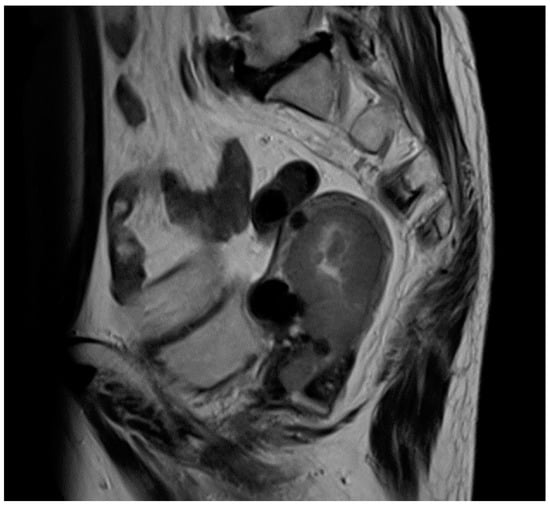

2. Case Presentation